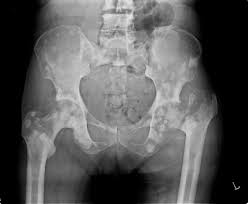

Bone Metastases Radiology Key

Bone Metastases Radiology Key from radiologykey.com